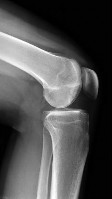

A 40-year-old pedestrian is struck by a motor vehicle, sustaining a severe valgus force to the knee. Computed tomography reveals a pure central depression fracture of the lateral tibial plateau, with the lateral cortical rim remaining intact. According to the Schatzker classification system, how is this fracture pattern classified?

Correct Answer: Schatzker III

Explanation:

Schatzker III fractures are pure central depressions of the lateral tibial plateau without an associated split of the lateral margin. Schatzker I is a pure wedge split of the lateral plateau. Schatzker II is a split-depression of the lateral plateau (most common). Schatzker IV involves the medial plateau. Schatzker V is a bicondylar fracture with intact metaphyseal-diaphyseal continuity. Schatzker VI involves metaphyseal-diaphyseal dissociation.